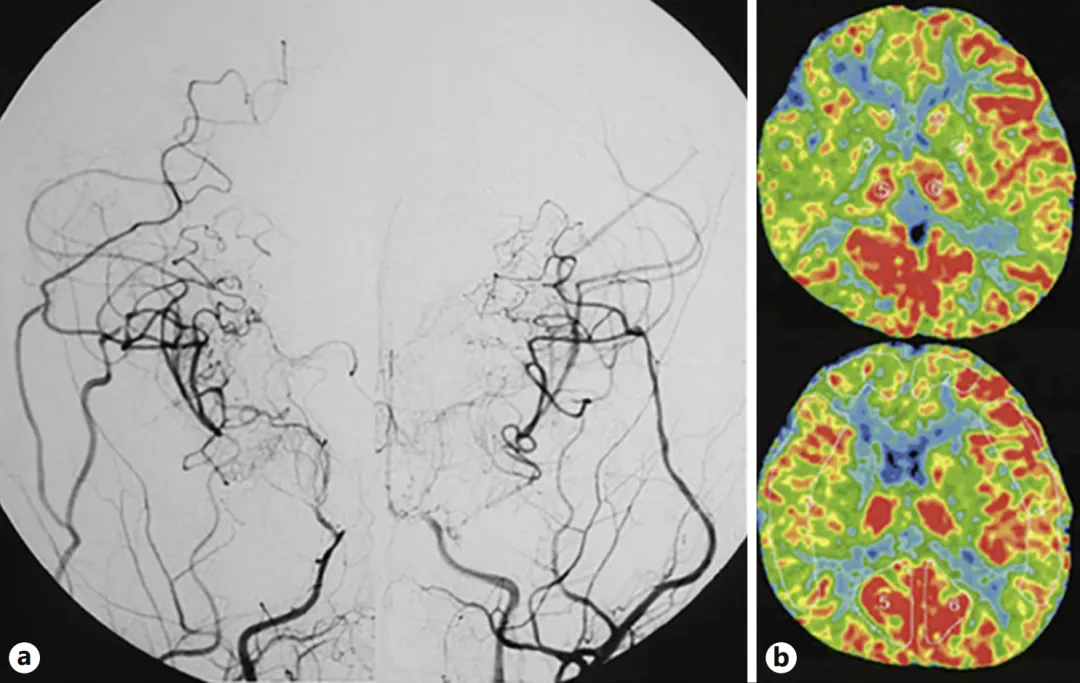

首次手术(右侧):将颞浅动脉额支、顶支与大脑中动脉M4段分支吻合(直接旁路),并行脑肌血管融合术(间接旁路)

二次手术(左侧):间隔一月后实施相同术式

术后随访显示侧支循环建立良好,基底节区异常血管减少,氙气计算机断层扫描(XeCT)证实双侧脑血流量改善。患儿术后恢复良好,长期服用阿司匹林,血压控制稳定。